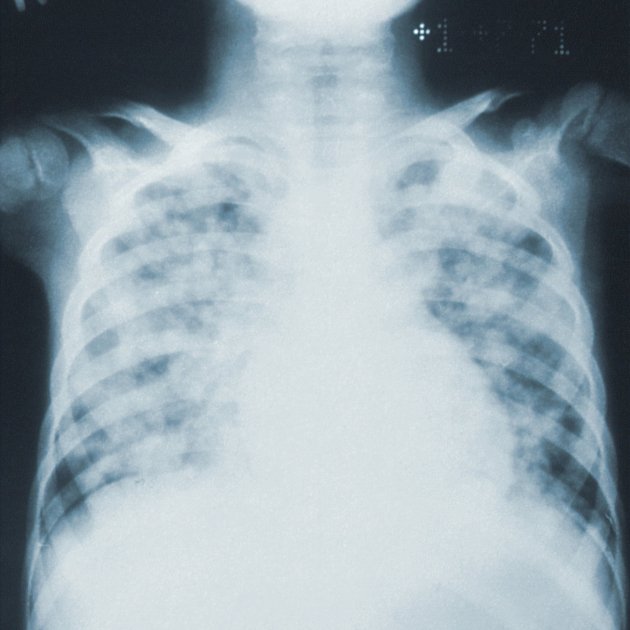

La Covid-19 pot afectar l'organisme de diferents maneres, però una de les més greus té lloc al pulmó. Un nou estudi està provant d'oferir una imatge més detallada de com es desenvolupa, revelant els mecanismes que poden derivar que la infecció es converteixi en letal i poden explicar les complicacions a llarg termini i mostrar com la Covid-19 es diferencia d'altres malalties infeccioses.

L'equip va examinar els pulmons de 19 persones que van morir de Covid-19 i es van sotmetre a una autòpsia ràpida poques hores després de la mort, durant la qual es van utilitzar pulmons i altres teixits de persones amb i sense Covid-19. En col·laboració amb investigadors de la Universitat de Cornell, els investigadors també van comparar les seves troballes amb els pulmons de pacients amb altres malalties respiratòries.

En comparació amb els pulmons normals, els pulmons dels pacients amb Covid eren plens de cèl·lules immunes anomenades macròfags. En general, durant una infecció, aquestes cèl·lules masteguen els patògens, però també regulen la intensitat de la inflamació, el que també ajuda a combatre el virus.

Amb la Covid-19, es produeix una expansió i activació incontrolada de macròfags, inclosos macròfags alveolars i macròfags derivats de monòcits. Estan completament desequilibrats i permeten que la inflamació augmenti sense control. Això dona com a resultat un cercle viciós en el qual entren més cèl·lules immunitàries que causen encara més inflamació, la qual cosa finalment fa malbé el teixit pulmonar. Aquests macròfags produeixen una citocina inflamatòria en particular, IL-1beta, a un ritme elevat. A diferència d'altres citocines com a IL-6, que sembla ser universalment prevalent en diverses pneumònies, la producció d'IL-1beta en macròfags és més pronunciada en la Covid-19 en comparació amb altres infeccions pulmonars virals o bacterianes.

Això és important perquè existeixen fàrmacs que redueixen els efectes de la IL-1beta. Alguns d'aquests medicaments ja s'estan provant en assajos clínics de pacients amb Covid. A més, en una infecció típica, un virus fa malbé les cèl·lules pulmonars, el sistema immunològic elimina el patogen i els rebutjos i el pulmó es regenera. Però amb la Covid, el nou estudi va trobar que el virus SARS-CoV-2 no només destrueix les cèl·lules epitelials alveolars importants per a l'intercanvi de gasos, sinó que la inflamació resultant també afecta la capacitat de les cèl·lules restants per regenerar el pulmó fet malbé. Encara que el pulmó encara conté cèl·lules que poden fer les reparacions, la inflamació atrapa permanentment aquestes cèl·lules en un estat cel·lular intermedi i les deixa incapaces de completar els últims passos de diferenciació necessaris per al reemplaçament de l'epiteli pulmonar madur.

Els investigadors també van trobar una gran quantitat de cèl·lules fibroblàstiques específiques, anomenades fibroblastos patològics, que creguin cicatrius ràpides als pulmons amb Covid-19. Quan les cèl·lules de fibroblastos omplen el pulmó amb teixit cicatricial, en un procés anomenat fibrosi, el pulmó té menys espai per a les cèl·lules involucrades en l'intercanvi de gasos i es fa malbé permanentment.